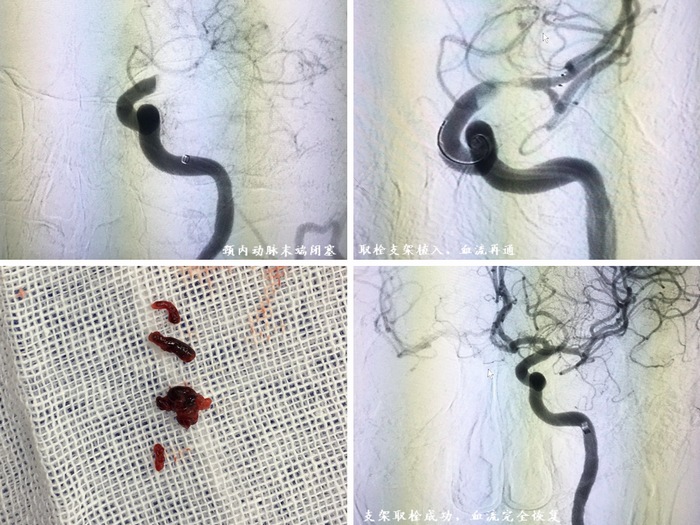

23:15分,宋大爷在静脉麻醉下穿刺成功,导丝就像一条训练有素的蛇一样,被耿晓坤副主任送入患者堵塞的血管。23:45分,在耿晓坤副主任和程哲医生的努力下,堵塞的血管被开通,取出了大量血栓。从穿刺成功到血管开通,仅用了30分钟!手术顺利完成,在场的所有人无不为这场战斗的成功而激动!刘凤智和耿晓坤两位医生来不及脱去铅衣就紧紧地拥抱在了一起!当大家脱下了沉重的铅衣,汗水早已浸透了手术衣……然而这些汗水换来的是患者平稳的生命体征,瘫痪的右侧肢体在刺激下已经有了反应,这一切都是值得的!两位术者并没有片刻的休息,在与家属短暂交流后就一路护送着宋大爷来到ICU进行下一步治疗。